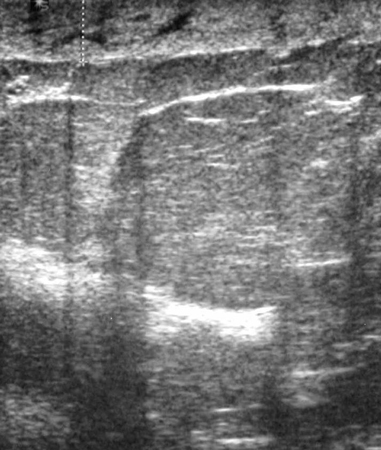

Os cistos simples são totalmente anecoicos, distintos do tecido mamário circundante na ultrassonografia de mama e benignos.[18][Figure caption and citation for the preceding image starts]: Imagem ultrassonográfica de um cisto simplesCortesia do Dr. Lane Roland, Universidade de Louisville; usado com permissão [Citation ends].

Os cistos complexos estão associados à septação ou detritos celulares internos e devem levantar suspeitas de neoplasia maligna. As diretrizes da National Comprehensive Cancer Network (NCCN) recomendam biópsia percutânea com agulha grossa de cistos complexos.[19][Figure caption and citation for the preceding image starts]: Imagem ultrassonográfica de um carcinoma complexoCortesia do Dr. Lane Roland, Universidade de Louisville; usado com permissão [Citation ends].